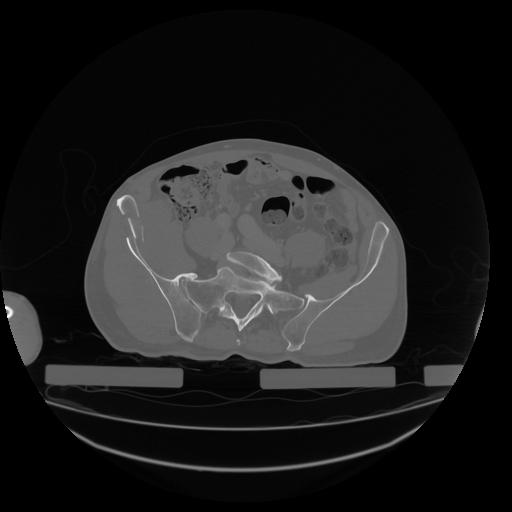

34 CUERPO,CE,Vol,1.0,CUERPO,,